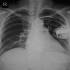

Pacemaker röntgenfelvételen

Aranybevonatú pacemakert ültettek egy betegbe Pécsen